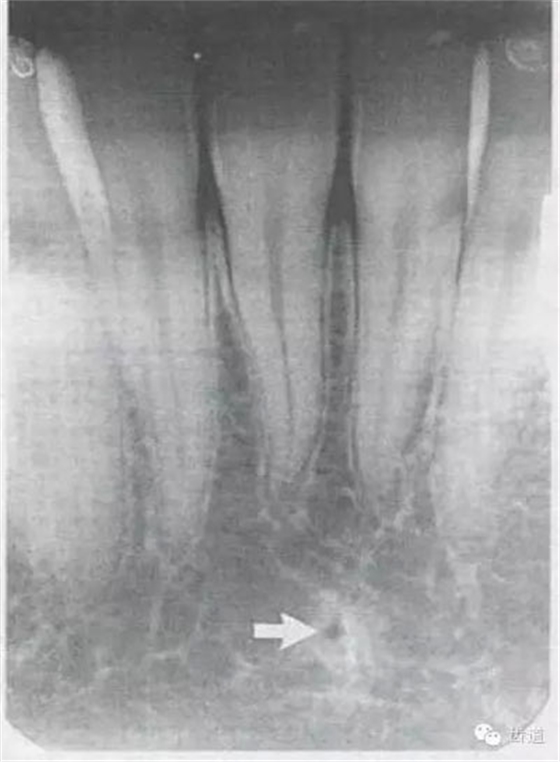

常見(jiàn)于下頜前牙區(qū),在牙根之間的牙槽骨內(nèi)并與牙長(zhǎng)軸平行的密度低的條狀影像。此為小血管進(jìn)入牙槽突的影像。